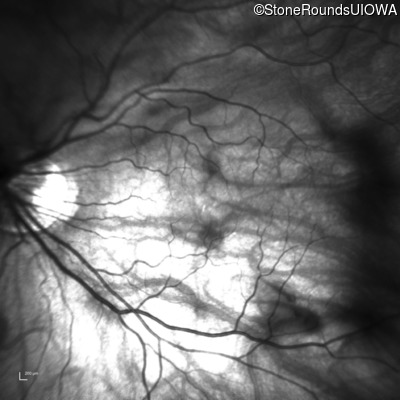

XL Congenital Stationary Night Blindness (IA2fi)

Age at visit: 25 years

This 25 year old man had pronounced esotropia noticed at six months of age. As a toddler, his parents noticed that he could not see well in dim light.

XL Congenital Stationary Night Blindness NYX Leu307Arg CTG>CGG   XL